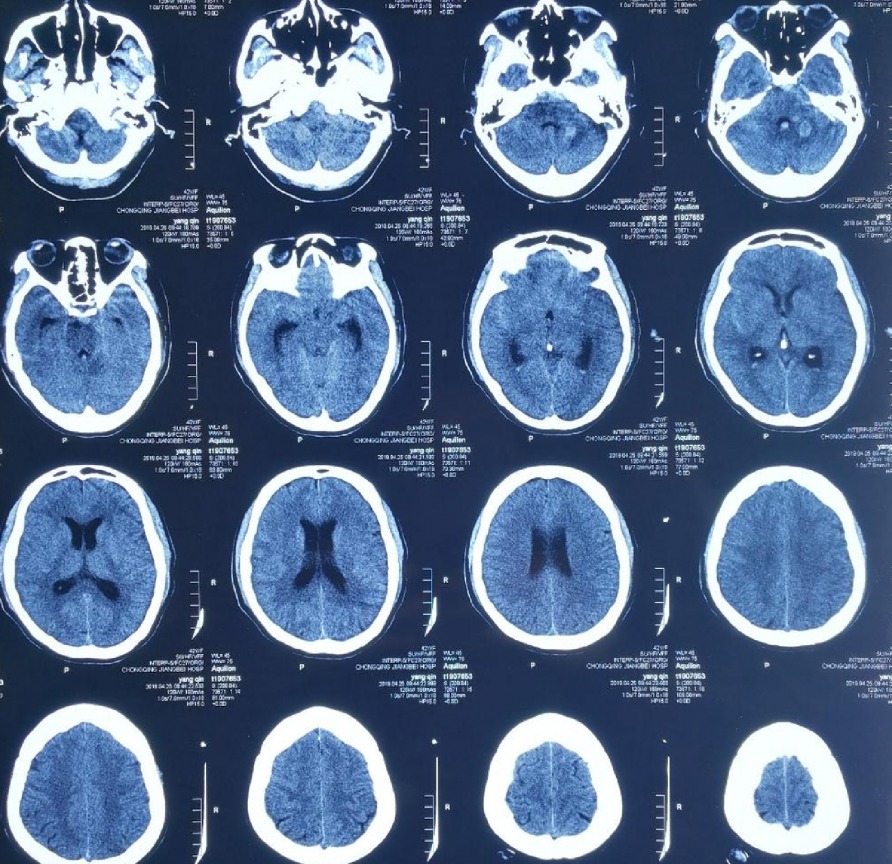

第⼀次CT显⽰:小脑出⾎,蛛⽹膜下腔出⾎,第IV脑室内出⾎

本次出⾎CT

⼊院CT显⽰:桥脑旁有出⾎